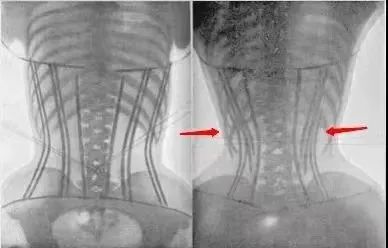

公众号丁香医生也曾晒出过一组X光片,能清楚地看到腰部被收紧时胸廓脊柱的改变,“原本正常的肋骨被向内、向下挤压,甚至带动脊柱出现扭转。”

▲ 弯曲的脊柱。图 / 丁香医生